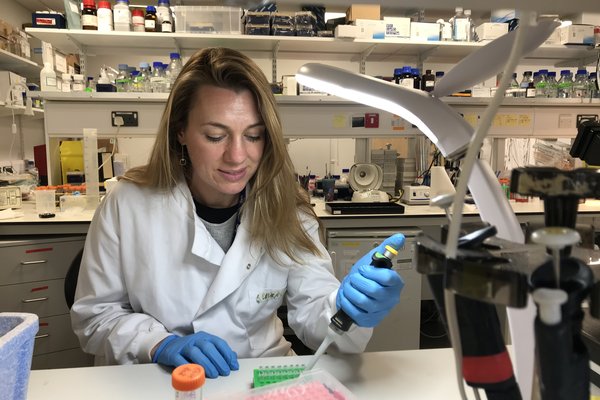

Funded by Wellbeing of Women, Dr Sarah McClelland has been investigating why some of the most common ovarian cancers become resistant to chemotherapy